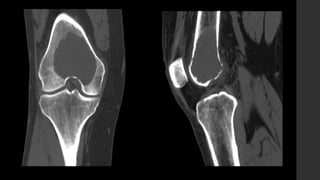

Tumor de Células Gigantes.

Murphey MD, Nomikos GC, Flemming DJ et-al. From the archives of AFIP. Imaging of giant cell tumor and giant cell reparative granuloma of bone: radiologic-pathologic correlation. Radiographics. 21 (5): 1283-309.

• Se localizan en huesos largos y sólo en núcleos de osificación cerrados, cercanos a

la superficie articular (84 – 99% <1cm).

• Son lesiones bien definidas excéntricas con margen no esclerótico.

• RX y TC 

 Zona de transición delgada sin esclerosis periférica.

 La corteza adyacente está adelgazada, expandida o deficiente.

 Reacción perióstica sólo en 10 - 30% de los casos.

 Puede presentar masa de tejidos blandos.

 Puede haber fracturas patológicas.

 No presentan matriz calcificada.

• IRM 

 T1 

 Componente sólido con señal intermedia a baja.

 Periferia con señal baja.

 T1+C 

 Realce de los componentes sólidos (lo distingue del quiste óseo aneurismático).

 Puede mostrar realce en la médula ósea adyacente.

 T2 

 Señal alta heterogénea con áreas de señal baja (debido a hemosiderina y fibrosis).

 Si hay componente quístico óseo aneurismático puede mostrar niveles líquido – líquido.

 Si hay señal alta adyacente a la médula ósea puede deberse a edema.